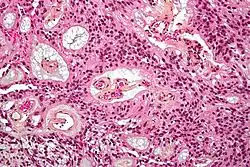

Micrograph of a myxopapillary ependymoma. HPS stain.

About 10% of ependymomas are benign myxopapillary ependymoma (MPE).[8] MPE is a localized and slow-growing low-grade tumor, which originates almost exclusively from the lumbosacral nervous tissue of young patients.[8] On the other hand, it is the most common tumor of the lumbosacral canal comprising about 90% of all tumoral lesions in this region.[9]

The World Health Organization classifies ependymomas as Grade I-III. Grade I tumors are low-grade and include the subependymoma subtype, which is more common in adults. Grade II tumors include myxopapillary and conventional ependymoma, which are identified by the presence of perivascular pseudorosettes. Grade III anaplastic ependymomas are the most severe and fast-growing tumors.[4]